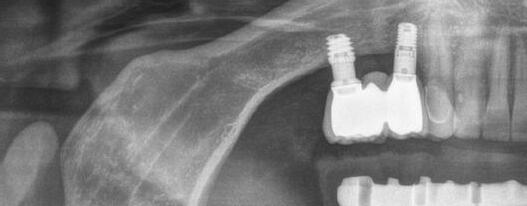

En la ortopantomografía se aprecia una dentición permanente a falta de la erupción de los 2os y 3 os molares, así como una asimetría ósea con rama y cóndilo mandibular izquierdo menos desarrollado (figura 9), causante de la asimetría facial descrita anteriormente.

Exploración radiológica

Mediante CBCT constatamos atrofias óseas severas y disminución de soporte óseo periodontal en relación con las piezas dentales.

procediendo a realizar una solicitud de encargo a través de un formulario. Antes de 72 horas recibimos una propuesta terapéutica. En ella se facilitan vistas 3D detalladas, así como valoraciones y consideraciones a tener en cuenta durante el fresado y la inserción de los implantes (Figuras 9 a 19). Decidimos realizar extracción de todas las piezas remanentes, dada su nula viabilidad a corto-medio plazo y en Bego (a través del portal) proponen mantener 3 piezas (las más viables técnicamente) en cada arcada para proporcionar el anclaje óptimo de la